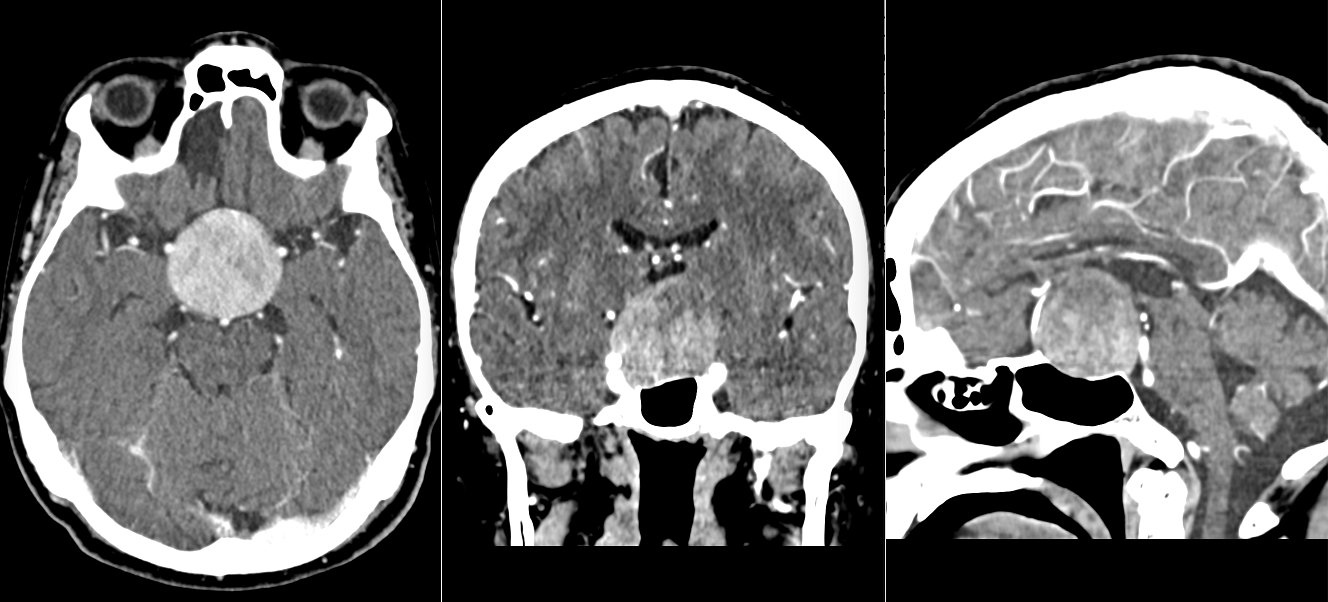

a) Tomografia computerizată (CT)

- Reprezintă adesea prima investigație efectuată în urgență, mai ales dacă pacientul se prezintă cu simptome acute (de exemplu, crize, semne de hipertensiune intracraniană).

- Este utilă pentru detectarea rapidă a unei mase tumorale, hemoragii sau efecte de masă.

- Poate fi efectuată cu sau fără substanță de contrast (iod).